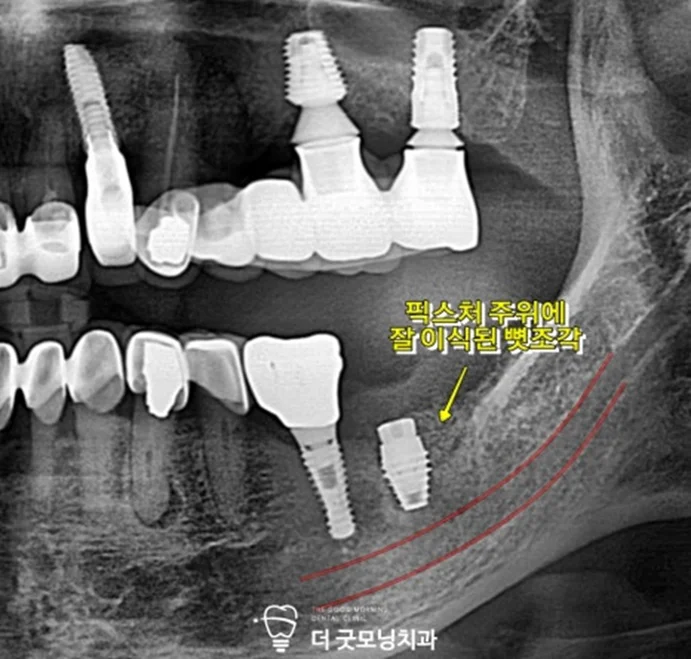

▲ 재식립 직후 엑스레이 – 하치조 신경관에 영향 없이 이식재 충진 확인

식립 후 촬영한 엑스레이에서 하치조 신경관에 영향을 주지 않고 픽스처 주위에 뼛조각이 잘 이식된 것을 확인하였습니다.